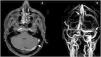

During hospitalization, lupus enteritis was diagnosed on day 4 due to the presence of abdominal pain, diarrhea and a contrast-enhanced CT scan with a target sign in the distal ileum (Fig. 1). In addition, due to an episode of thunderclap headache (day 7) a brain angioresonance was performed, which detected thrombosis at the confluence of the transverse, left sigmoid and superior sagittal venous sinuses (Fig. 2; Table 1). Due to these findings, immunoglobulin infusion and anticoagulation were started.

Contrast enhanced magnetic resonance imaging of the brain. A) Postgadolinium T1, partially recanalized venous thrombosis at the confluence of the left transverse and sigmoid sinuses (white arrow). B) Venous resonance, central flow defect at the junction of the left transverse and sigmoid sinuses and in the posterior aspect of the superior sagittal sinus (white arrows).